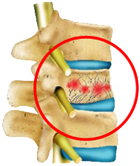

腰椎圧迫骨折

くしゃみや荷物を持つ、転倒などちょっとした動作がきっかけで起こり、背中や腰に強い痛みを感じます。「背が低くなった」「背中が丸くなった」と感じる場合も要注意です。

骨粗しょう症が原因で知らないうちに背骨が折れる“いつのまにか骨折”もあり、放置すると慢性的な腰痛や足の力の低下につながります。

安静で痛みが和らぐこともありますが、背骨が押しつぶされた状態のため再骨折の危険もあります。